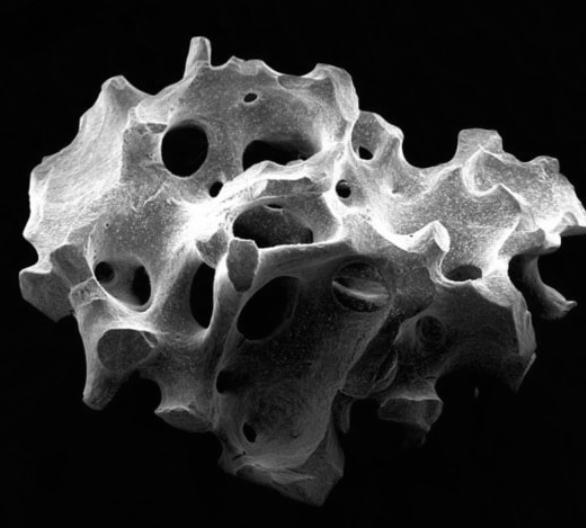

Bone Grafting Material - Microscopic Structure

طعوم عظمية

زراعة كتل عظمية للعيوب الكبيرة

تجديد موجّه

نمو عظمي بمساعدة الأغشية لنتائج دقيقة